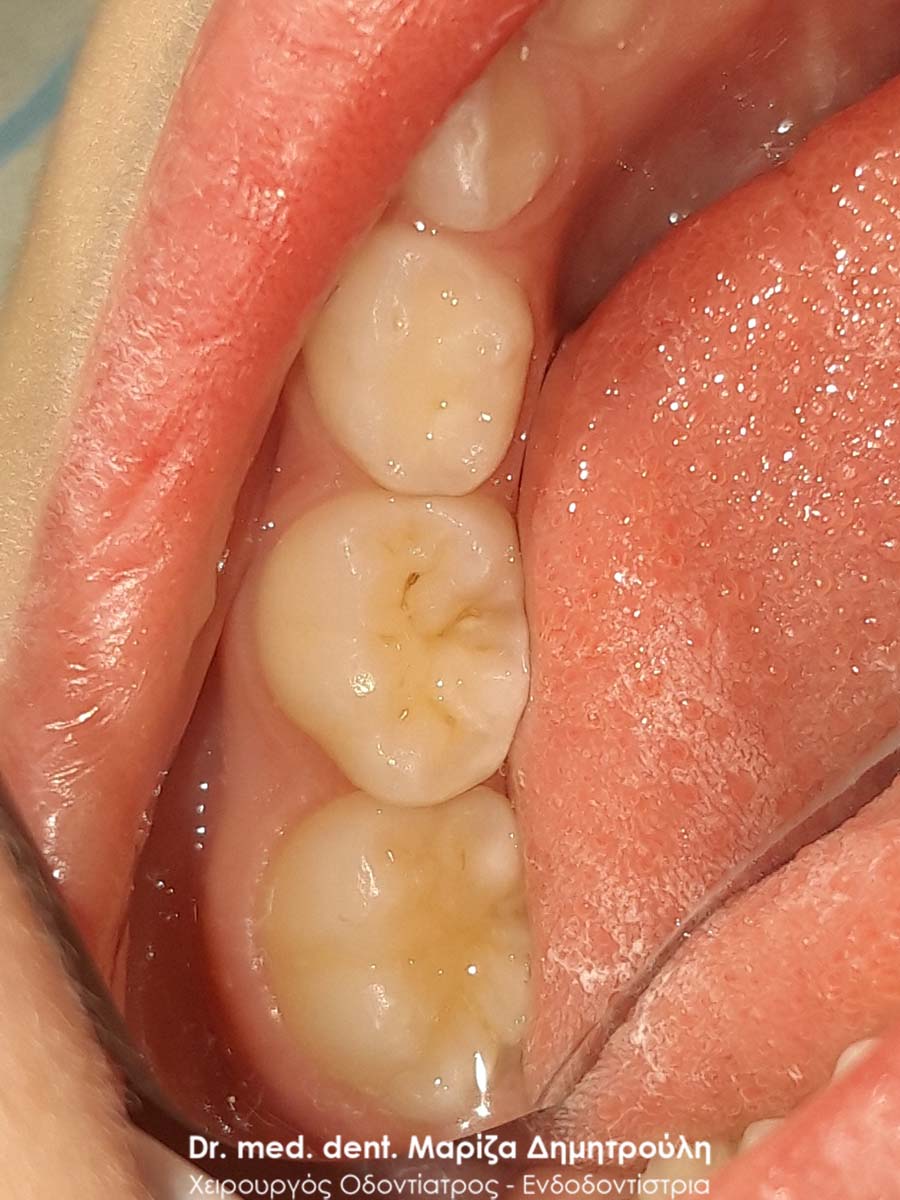

Αρχική κλινική εικόνα της δεξιάς πλευράς της κάτω γνάθου

Λευκά σφραγίσματα στη δεξιά πλευρά της κάτω γνάθου με τη μέθοδο stamp technique